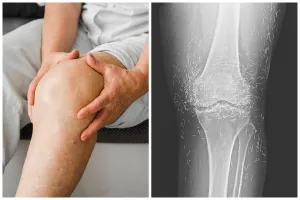

Bikin syok, dokter ini temukan benang susuk emas di lutut pasien saat lakukan rontgen